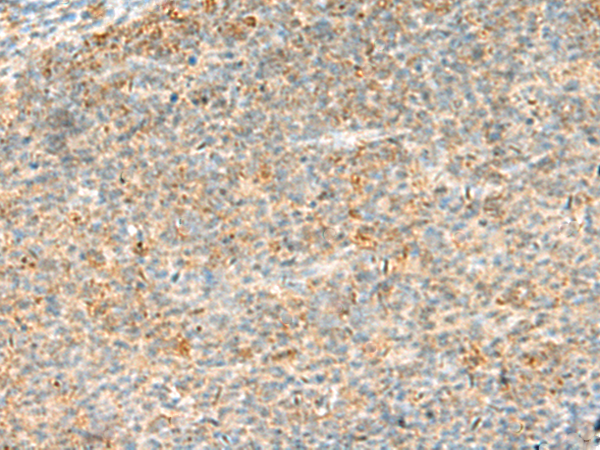

分类: 科研抗体货号: P13570别名: B7y; B7H7; B7-H5; B7-H7应用: IHC反应种属: Human